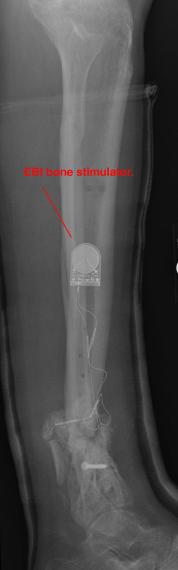

Preoperative X-Rays of the left ankle

These x-rays were taken just prior to surgery where Dr. Saunders planed to build up the left ankle with material, to repair any alignment issues

and to implant an electrical device that promotes bone growth and healing (like the EBI OsteoGen-M device shown in the last photo).

The ghost image around the leg is from the cast that was added following Liam's X-Box break. In some of the images, it can be seen

that Liam has removed the small window cover that was cut to allow access for the use of an Exogen ultrasonic bone-healing device.

Postoperative (12th) images of left ankle

The images displayed here were created at various appointments following surgery performed by Dr. Daniel Saunders. In the X-Ray you can see

where Dr. Saunders has removed the fibula plate, joined the tibia and fibula with a screw, built-up the area of the tibia where previously

there was considerable absence of bone and lastly added the EBI OsteoGen-M Bone Stimulator (dual lead). The photos show the left side site

where the fibula plate was removed, the top site where donor bone, bone filler material and the stimulator were added and the right side

where the tissue has burst because of swelling. Liam was placed on an IV drip of Vancomycin following surgery to combat the potential onset

of Osteomyelitis. The image of the cast includes the fibula plate that was removed during surgery. The next images were taken later and show

that the staples and stitches were removed. In one of the images, you can see Liam's wife Madeline helping with leg cleanup and in one image

can be seen the EBI representative after being put to work (holding up the left leg while the latest cast cures) by Dr. Saunders. Later shots show

a healing tissue burst site with some overgrowth and Dr. Saunders cauterizing the overgrowth. Bones shifting too much (shown in X-Rays). The

last images are of the left ankle prior to the 13th surgery.